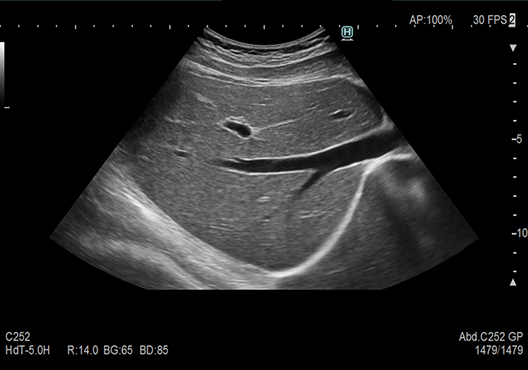

この度、新しい超音波診断装置「富士フィルム製 ARIETTA 750SE」を導入いたしました。

画像の正確性・診断の再現性・検査の効率性を追求した最新式の超音波診断装置です。

今まで以上に画像診断検査の精度向上が期待できます。